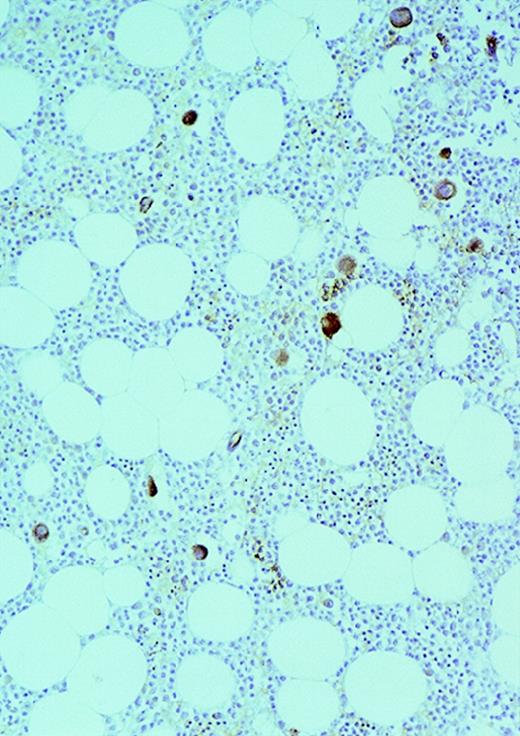

The patients with AML consisted of 8 women and 12 men; the control patients consisted of 12 women and 8 men. The mean age of the AML patients was 59 years (range, 24-87 years). In the control group, the mean age was 49 years (range, 27-71 years). The FAB distribution of the AML cases was as follows: 2 M0, 6 M1, 6 M2, 4 M4, and 2 M7. The cellularity (average ± SEM) was 78% ± 26% (range, 25% to 100%) and 49% ± 8% (range, 35% to 65%) for AML and normal marrows, respectively (P < .0001). Using ULEX-E staining, AML marrows had (average ± SEM) 8.3 ± 3.6 vessels/mm (range, 3.7-19.3) while normal marrows had 4.3 ± 1.8 vessels/mm (range, 1.6-7.9). Using vWF staining of the same specimens, AML marrows had 8.6 ± 3.0 vessels/mm (range, 3.7-15.8) and normal marrows had 4.9 ± 2.2 vessels/mm (range, 1.5-10.1). The differences between the numbers of vessels/mm in AML and normal marrows were highly significant (P < .0001 for both ULEX-E and vWF staining). ULEX-E and vWF exhibited similar staining patterns. Figures1 and 2 show examples of vascularity in normal and AML marrows.

Vascularity of normal and AML marrow specimens.

Normal or AML bone marrow samples were stained with H&E or for vWF expression (see Methods) for vessel scoring. Legends (all ×200): A = normal bone marrow with H&E stain; B = normal bone marrow with vWF stain; C = AML bone marrow with H&E stain; D = AML bone marrow with vWF stain. The normal bone marrow shows strong staining for vWF in megakaryocytes but no evidence of increased vessels. The AML marrow has significantly more vessels than the normal marrow. These sections are representative of the whole series.